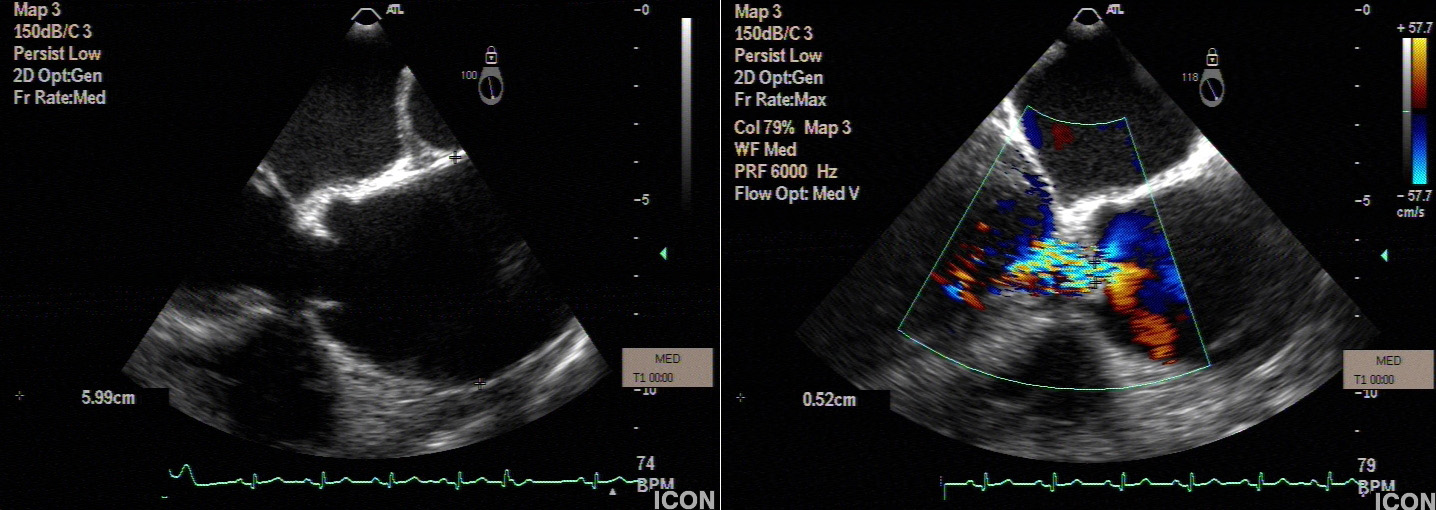

Preoperative echocardiography demonstrated a dilated sinutubular junction (STJ), preserved sinus dimensions and moderate to severe aortic valve insufficiency with central regurgitant jet.

During surgery, comprehensive visual assessment of aortic cusp configuration revealed prolapse of the non-coronary cusp, which was repaired by appropriate techniques. Ascending aorta pathology was corrected with sinutubular junction remodelling (STJR).